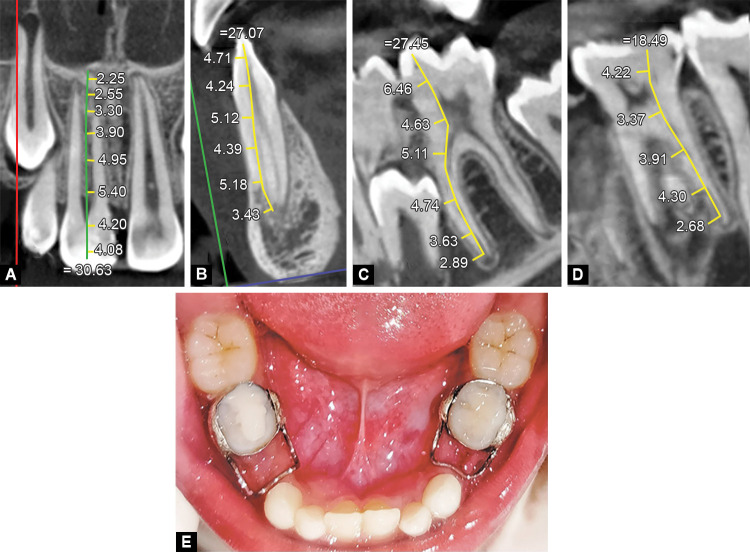

Case description: This article highlights the first ever reported case of familial, nonsyndromic, generalized radiculomegaly affecting the primary and permanent dentitions in a 13-year-old male who had visited the Department of Pedodontics and Preventive Dentistry for a dental checkup. Clinical examination revealed a delay in eruption since his dentition was inconsistent with his age. An orthopantomograph showed the presence of primary and permanent teeth with longer roots than usual.

Conclusion: A diagnosis of radiculomegaly was made from full-mouth CBCT tooth measurements that confirmed longer roots. Orthopantomographs of his sibling and father revealed similar findings.